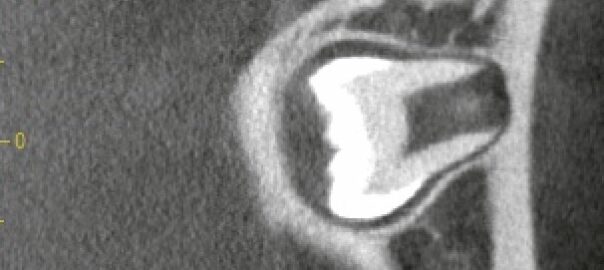

上顎洞に近接した深い埋伏上顎親知らず|CTで判明した「逆向き」の歯も同日抜歯した症例

こんにちは。東京都中央区銀座5丁目にある 【親知らず・顎関節症クリニック銀座(通称:オヤアゴクリニック)】です。 当院は以下の3つに特化した歯科クリニックです。 * 親知らずの抜歯 * 顎関節症の治療 * アスリートのた … 続きを読む 上顎洞に近接した深い埋伏上顎親知らず|CTで判明した「逆向き」の歯も同日抜歯した症例